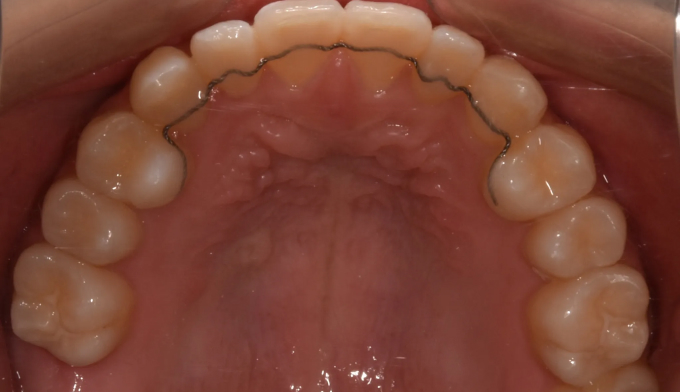

덧니

얇은 입술과 뒤로 들어간 입술을 가지고 있기 때문에 발치를 하지 않고 확장과 후방이동을 통해 최대한 공간을 마련하여 교정하기로 하였습니다.

덧니뿐만 아니라 앞니의 교합이 좋지 않아 윗니가 아랫니를 덮지 못하는 개방교합도 동시에 나타납니다.

총 교정기간은 21개월입니다.

원래 앞니의 길이가 위아래로 긴 형태를 가지고 있어서 치아의 길이를 조금 더 줄이면 보다 더 심미적이고 조화로운 형태를 나타냈을텐데, 환자가 치아의 형태를 바꾸길 원하지 않아 조금은 아쉬운 결과를 보입니다.